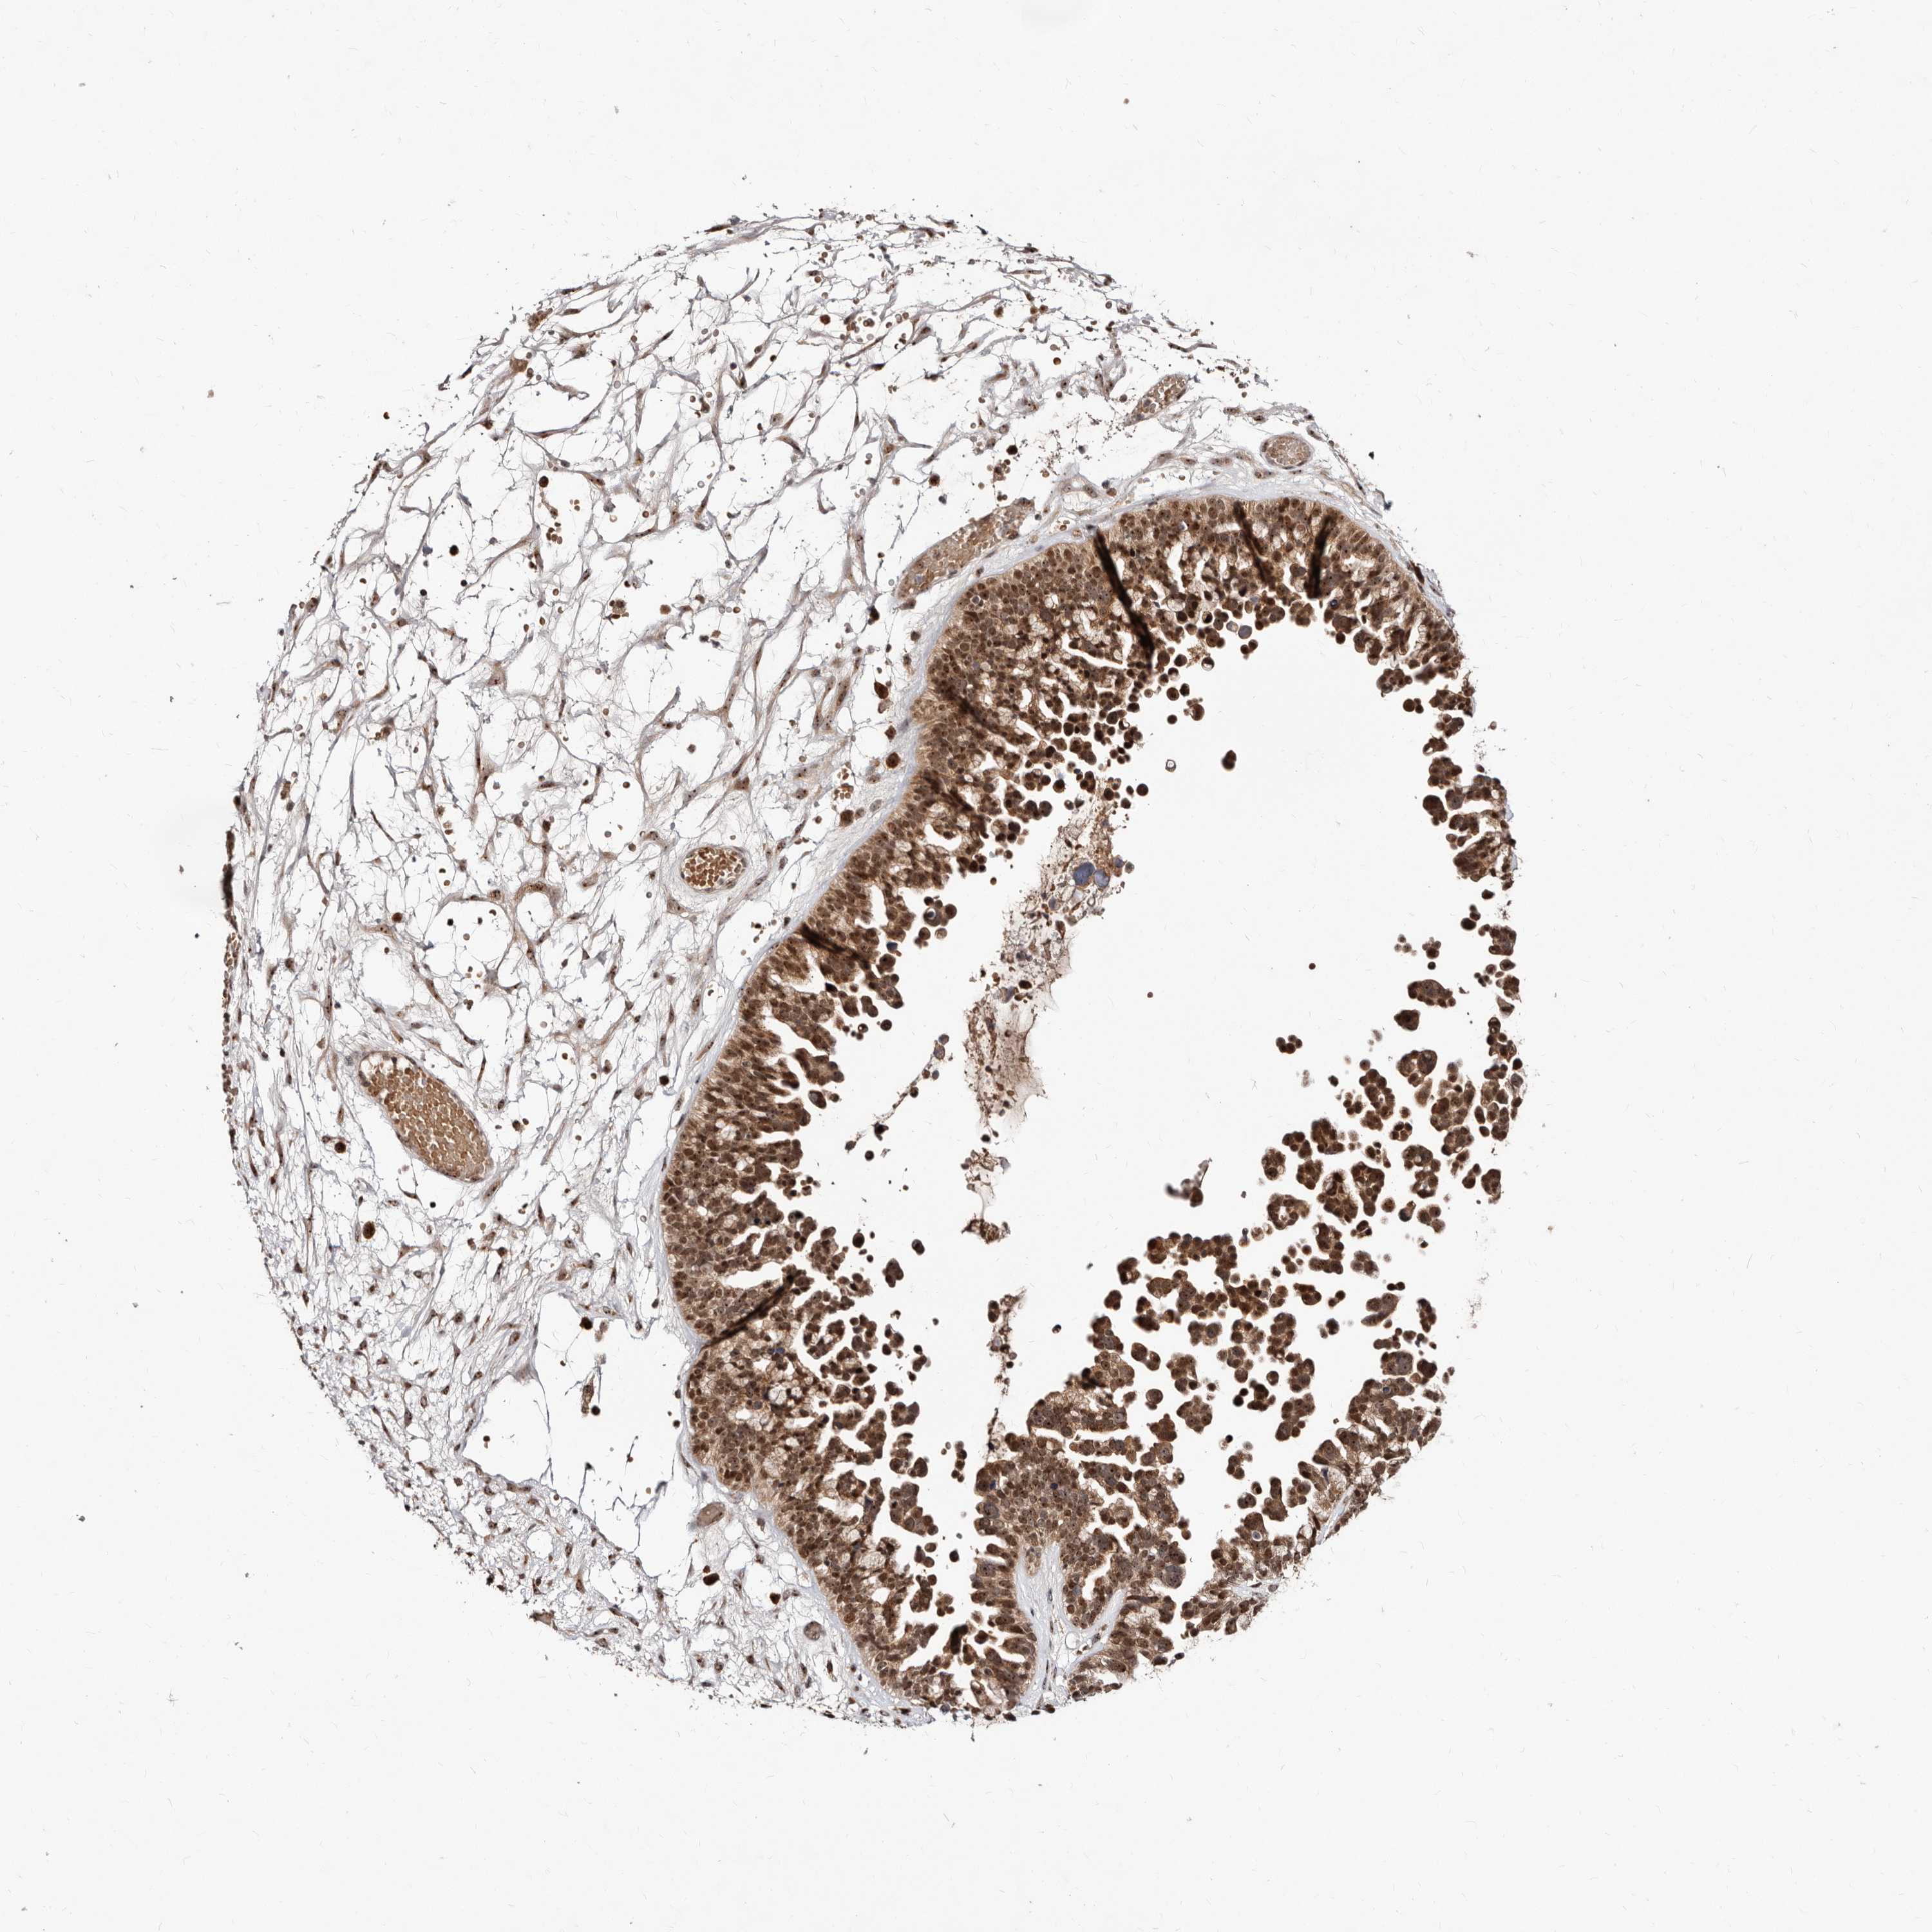

OVARIAN CANCER - Protein expressioni

A mouse-over function shows sample information and annotation data. Click on an image to view it in a full screen mode. Samples can be filtered based on level of antibody staining by selecting one or several of the following categories: high, medium, low and not detected. The assay and annotation is described here.

Note that samples used for immunohistochemistry by the Human Protein Atlas do not correspond to samples in the TCGA dataset.

Antibody stainingi

Antibody staining in the annotated cell types in the current human tissue is reported as not detected, low, medium, or high, based on conventional immunohistochemistry profiling in selected tissues. This score is based on the combination of the staining intensity and fraction of stained cells.

Each image is clickable and will lead to virtual microscopy that enables deeper exploration of all samples and also displays staining intensity scores, fraction scores and subcellular localization as well as patient and tissue information for each sample.

Antibody HPA029165

Antibody HPA029167

Antibody CAB028574

Staining

High

Medium

Low

Not detected

Intensity

Strong

Moderate

Weak

Negative

Quantity

>75%

75%-25%

<25%

None

Location

Nuclear

Cytoplasmic/membranous

Cytoplasmic/membranous,nuclear

Cystadenocarcinoma, serous, NOS

Carcinoma, endometroid

Cystadenocarcinoma, mucinous, NOS

Carcinoma, NOS